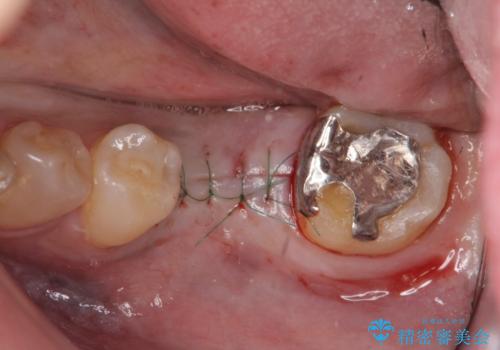

ブリッジや入れ歯といった周囲の歯の負担を増やす方法ではなく、より強大な咬合力にしっかりと耐え噛むことのできるインプラントを用いた機能回復を計画します。

今回の治療では、周囲の歯に負担を増やし破折リスクを高めるブリッジや入れ歯ではなくインプラント治療を選択しました。

- 外科手術のため、術後に痛みや腫れ、違和感を伴います